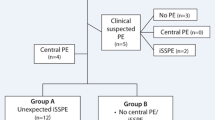

The results of the patient selection process in our study are shown in Fig. 1. From March, 14, 2020, to April 6, 2020, 211 patients were referred by the emergency department to undergo a chest CT for suspicion or assessment of COVID-19 pneumonia. A total of 146 (69%) patients had a final diagnosis of COVID-19 and 72 (49%) patients underwent CTPA and were included in our study. Thirteen (18%) patients had APE (APE group) versus 59 (82%) without APE (non-APE group). Of the 72 patients included in the study, 58 (80%) patients had a positive RT-PCR for SARS-CoV-2, 10 (14%) did not have RT-PCR (including three from the APE group), and 4 (6%) had a diagnosis based on the typical clinical and radiological presentation of COVID-19 with RT-PCR results negative for SARS-CoV-2 (two patients with a single sample including one patient from the APE group, and two patients with two negative RT-PCR including one from the APE group).

COVID-19 presents many clinical forms, from cases of pauci- or asymptomatic patients to cases of severe forms of COVID-19 pneumonia which may lead to the patient’s death [24]. The association between COVID-19 pneumonia and APE has already been described in patients hospitalized with severe to critical clinical type [13,14,15,16,17,18]. To the best of our knowledge, no study has yet evaluated the prevalence of APE in outpatients consulting to the emergency department for clinical suspicion or degradation of COVID-19 pneumonia. One case describes the discovery of APE in a COVID-19 patient with a mild clinical form presenting to the emergency department for hemoptysis [25]. In our study, we focused on patients presenting to the emergency department for suspected or worsening COVID-19 pneumonia. Among these patients, many presented not only a deterioration of their clinical state with dyspnea (68%), desaturation (67%), or chest pain (14%) but also an increase in D-dimer levels. These anomalies, although not specific, led us to complement our non-contrast chest CT scans with CTPA to eliminate APE. Of our 146 CT scans performed on COVID-19 patients, we complemented the examinations with 72 (49%) CTPA. Thirteen APE were discovered, representing a prevalence of 18% of the patients included in our study. Eight patients with APE had a severe to critical COVID-19 pneumonia but 5 of the 13 (38%) patients with APE had a moderate clinical form (Fig. 2). These results seem to confirm the association between COVID-19 and APE, even in non-severe and non-hospitalized COVID-19 patients.